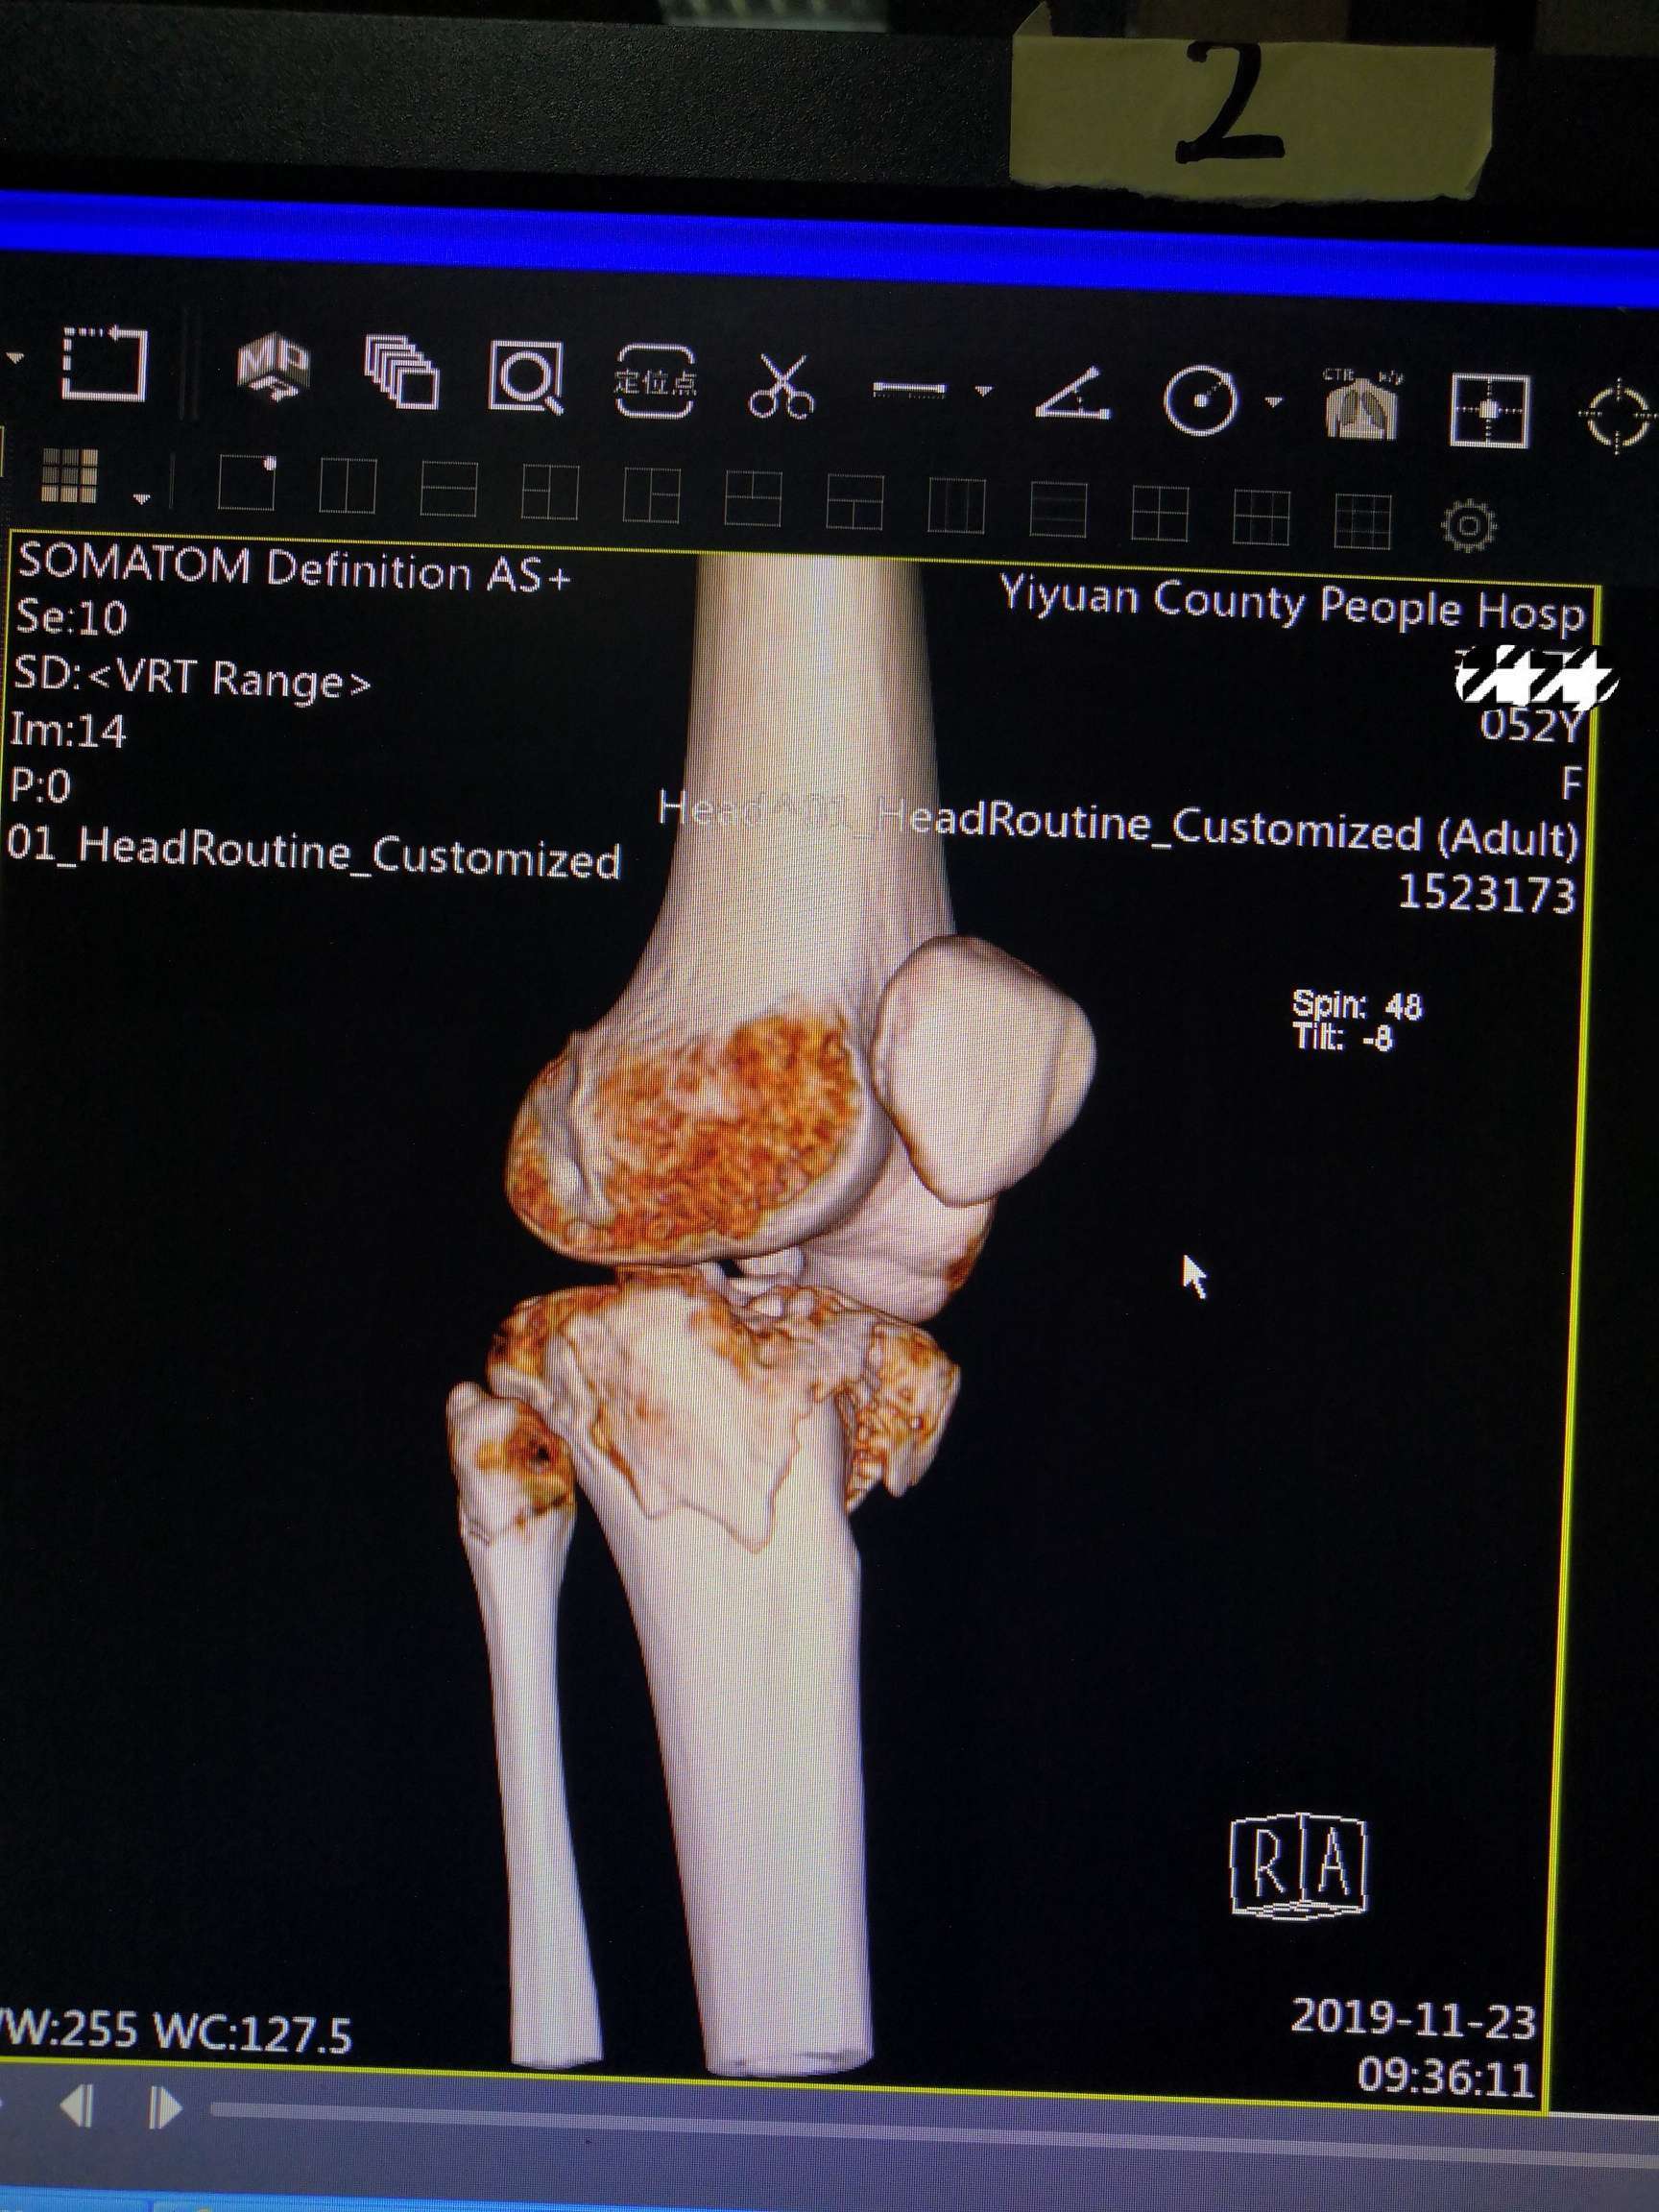

术前影像资料